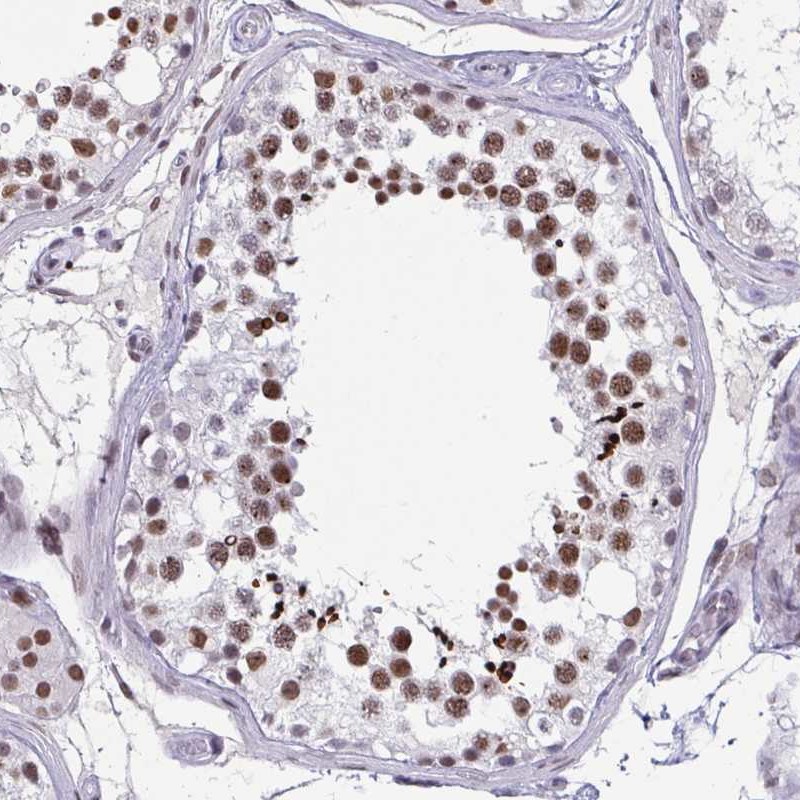

Immunohistochemistry analysis in human testis and liver tissues using Anti-CBFA2T2 antibody. Corresponding CBFA2T2 RNA-seq data are presented for the same tissues.